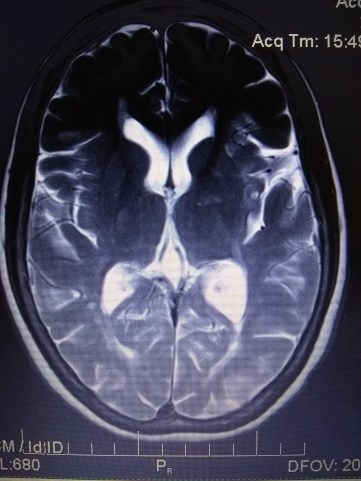

Nuclear Magnetic Resonance Imaging

NMRI 2018 June 18

AXIAL T2

SECTION 2/2

IMAGE 12/24

REPORT 2018 June 25: Sub-acute T2 hypersensitivity, left frontal lobe

TREATMENT 2018 June 25: 60mg oral steroids x 16 days. ACTIVITY 2018 June 25: bedrest x 16 days

and the texture of my brain

whose rippling white matter winds through the warp and grain